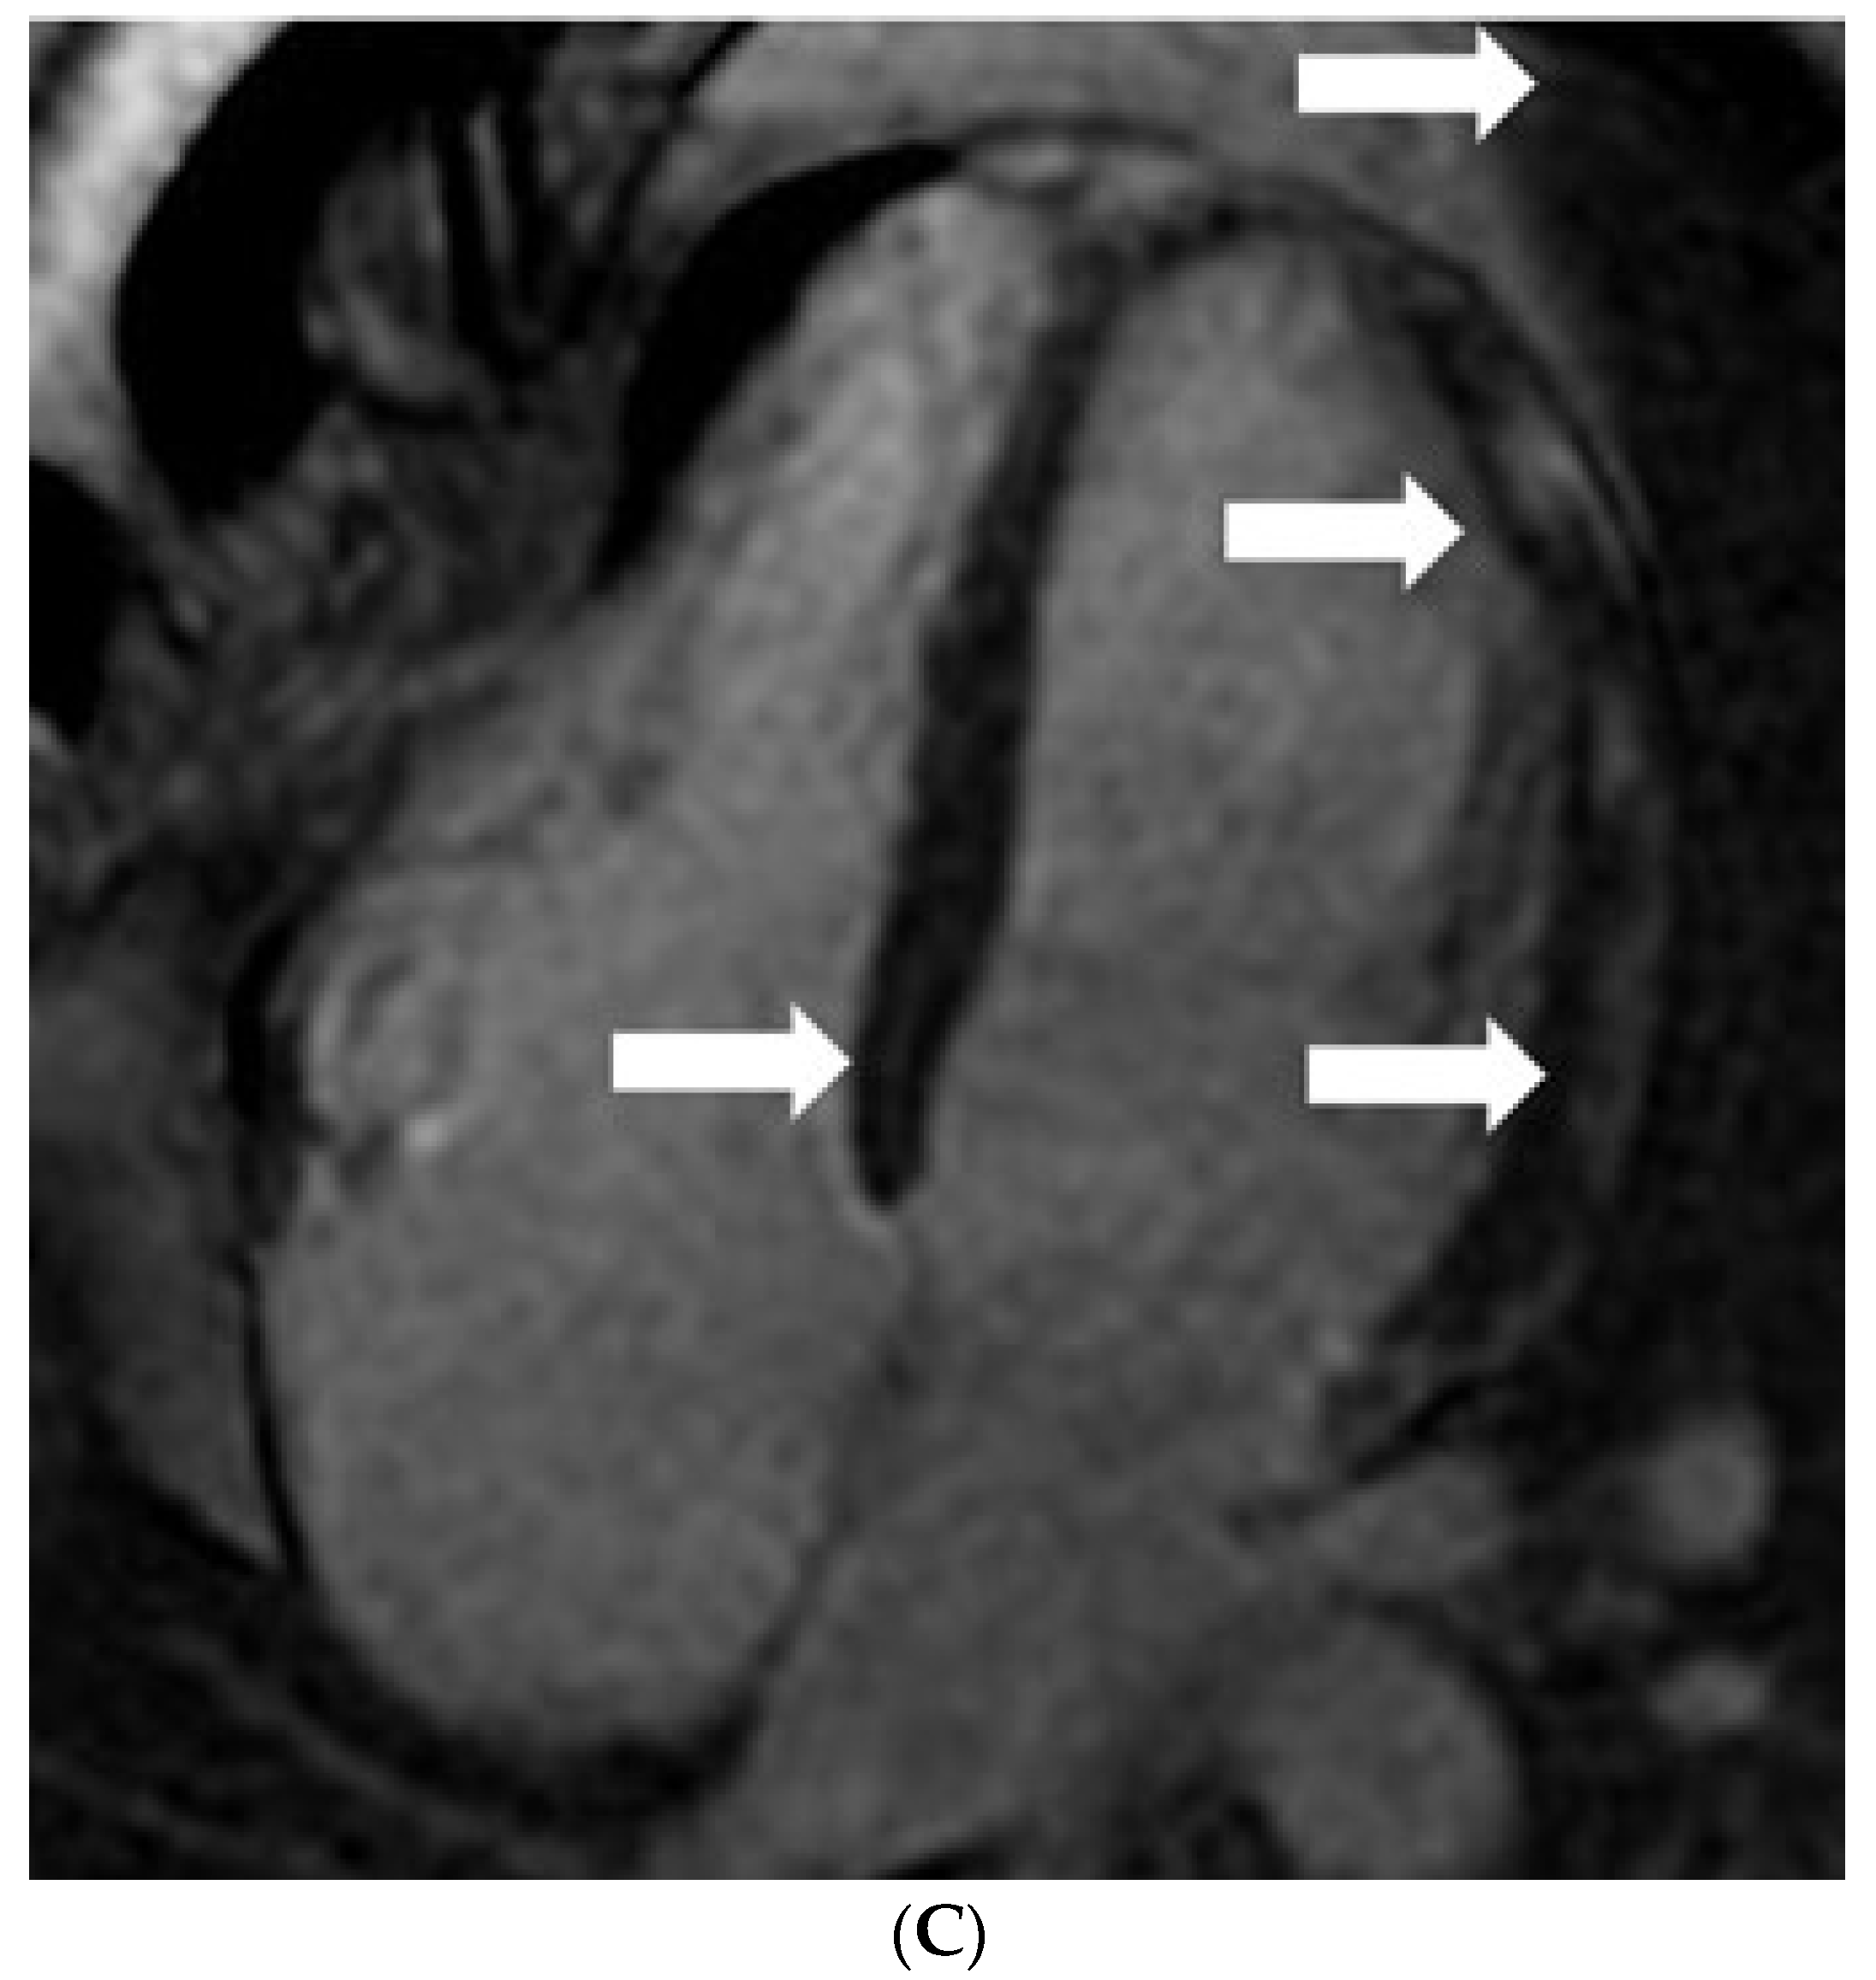

Post-RNA (mRNA) Vaccination Myocarditis: CMR Features

Das, K.M.; Mansoori, T.A.; Shamisi, A.A.; AlBastaki, U.M.; Gorkom, K.V.; Alkoteesh, J.A. Post-RNA (mRNA) Vaccination Myocarditis: CMR Features. Diagnostics 2022, 12, 1034. https://doi.org/10.3390/diagnostics12051034